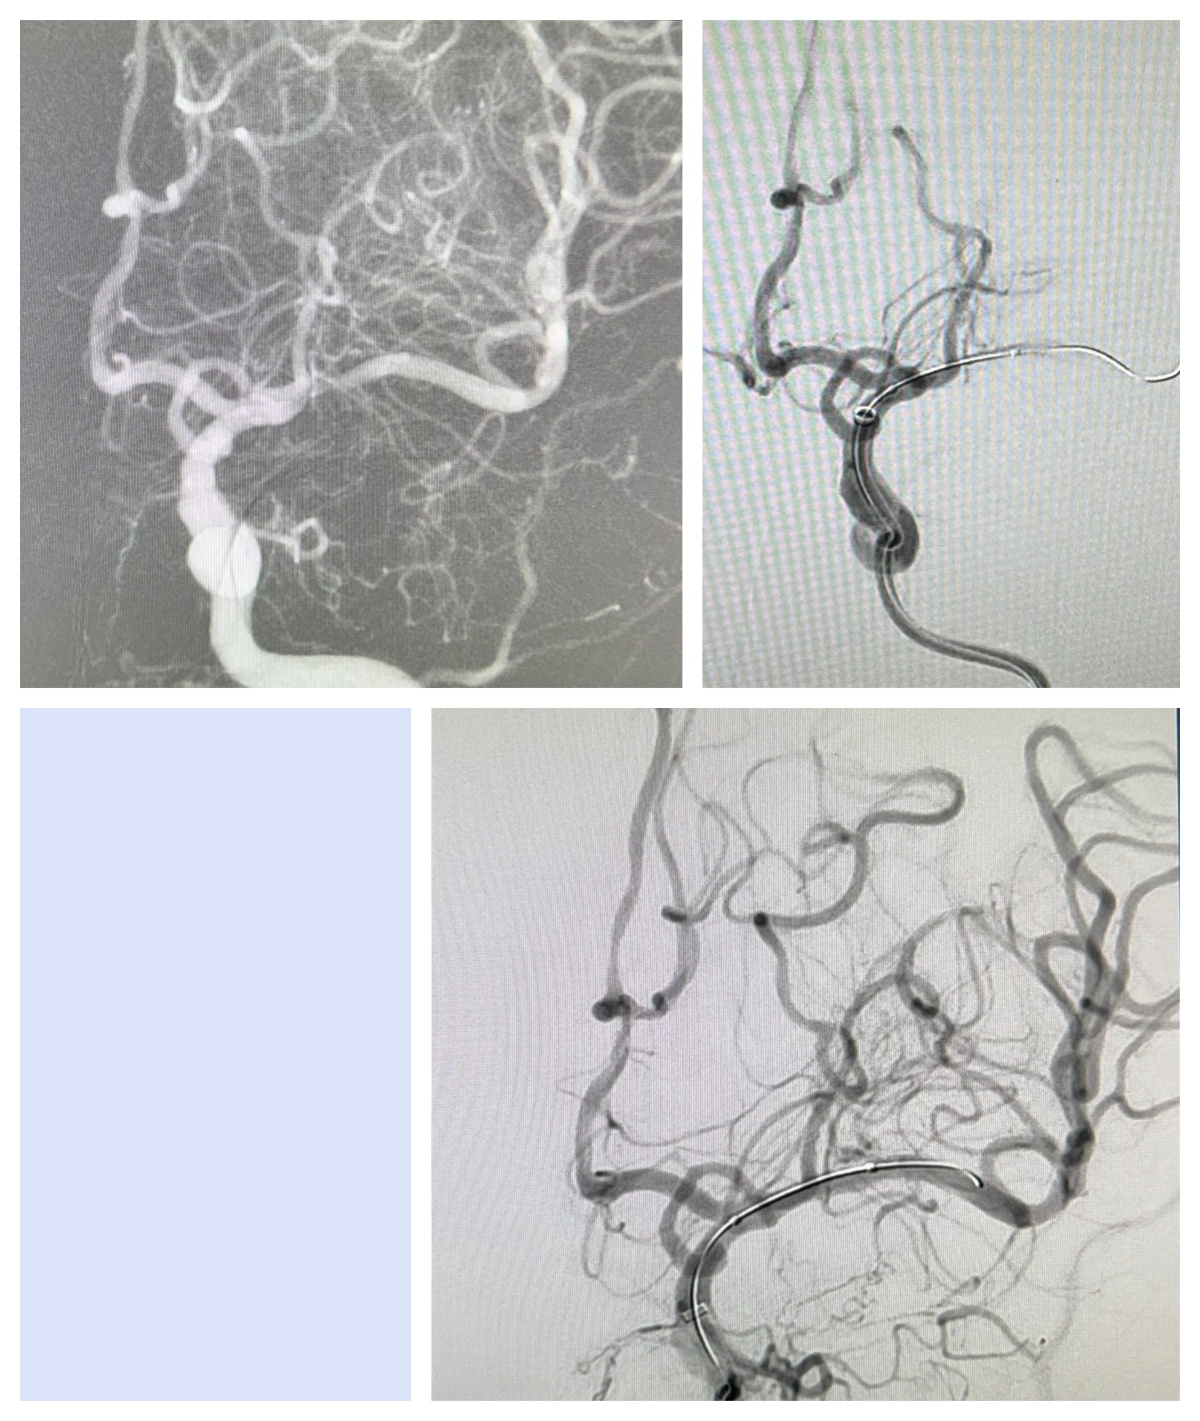

材料:8F指引导管、6F-125中间导管、0.035导丝、Rebar-18微导管、Avigo微导丝、2.0-15颅内球囊扩张导管

球扩后发现血流缓慢,使用欣维宁观察10分钟后无明显好转,拟再次提高压力再次扩张。

此次球扩后原狭窄处完全打开,恢复3级血流。

术后行Dynact检查,未见出血,回监护室监护治疗,镇静镇痛并控制血压,持续欣维宁泵入。